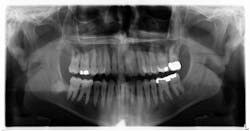

In this particular case, the patient was referred to an oral surgeon and the lesion was removed. Histology confirmed the diagnosis, and the patient has been seen on a regular basis without any complications or recurrent lesions. The bone has filled in nicely and no. 18 is vital. The coronal portion of no. 32 was removed due to the wrapping of the roots around the inferior alveolar nerve.